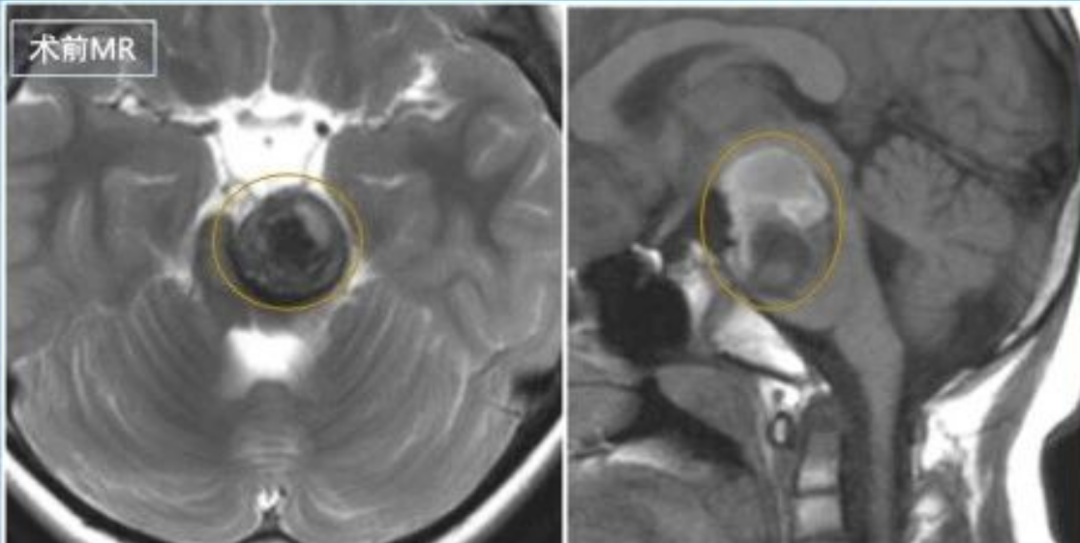

术前影像显示脑干脑桥左侧占位病变,锥体束受压,可见含铁血黄素环形成。